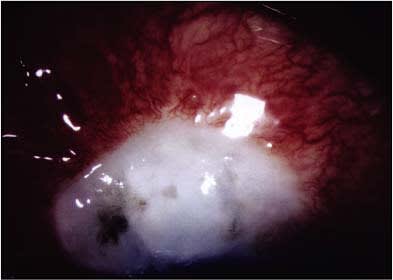

Figure 4. Endophthalmitis developed in this patient 2 months following glaucoma filtration surgery with mitomycin C. The patient was treated with pars plana vitrectomy surgery and intravitreal antibiotics. The infection was suppressed, though visual recovery was very limited at HM at 2 feet.